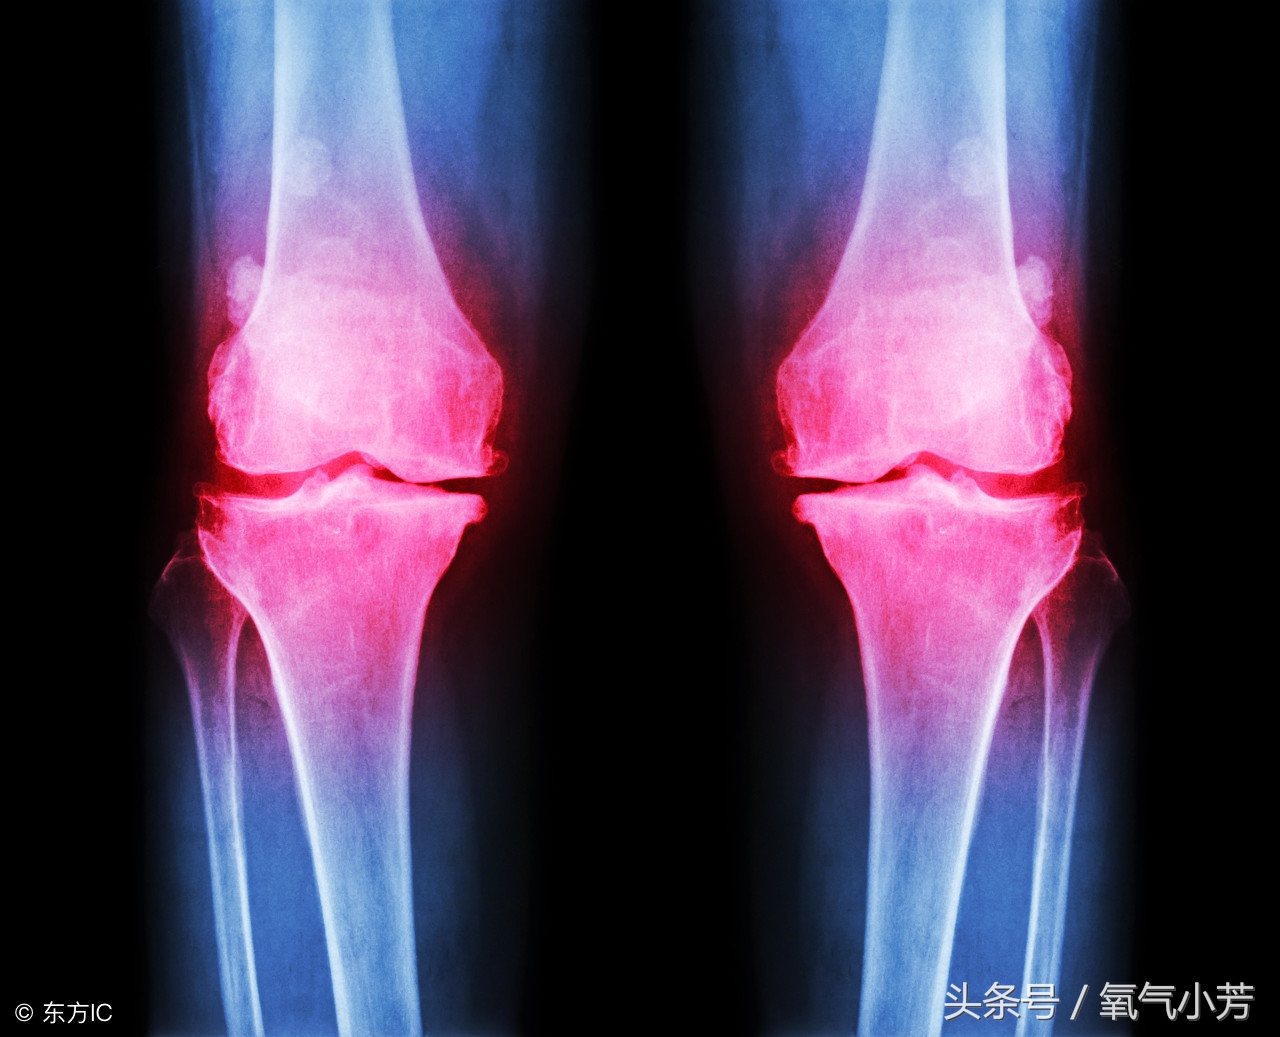

膝关节增生

骨质增生的出现,本质上是好事!真的。它往往出现在关节部位,比如:颈椎增生、腰椎增生、膝关节增生等。关节,是身体活动的基础,各个关节都是活动量比较大的。

关节因为长期受累会出现不稳定,这个时候就出现骨质增生。骨质增生可以通过增加骨骼接触面积的方式来减少骨骼单位面积上的压力,从而帮助我们来减轻负担。

本意是好的,但是有点帮倒忙了。骨质增生的出现,让身体非常不舒服,从而引发无菌炎症,继而出现多种症状:肌肉酸疼、神经疼痛、活动受限等。